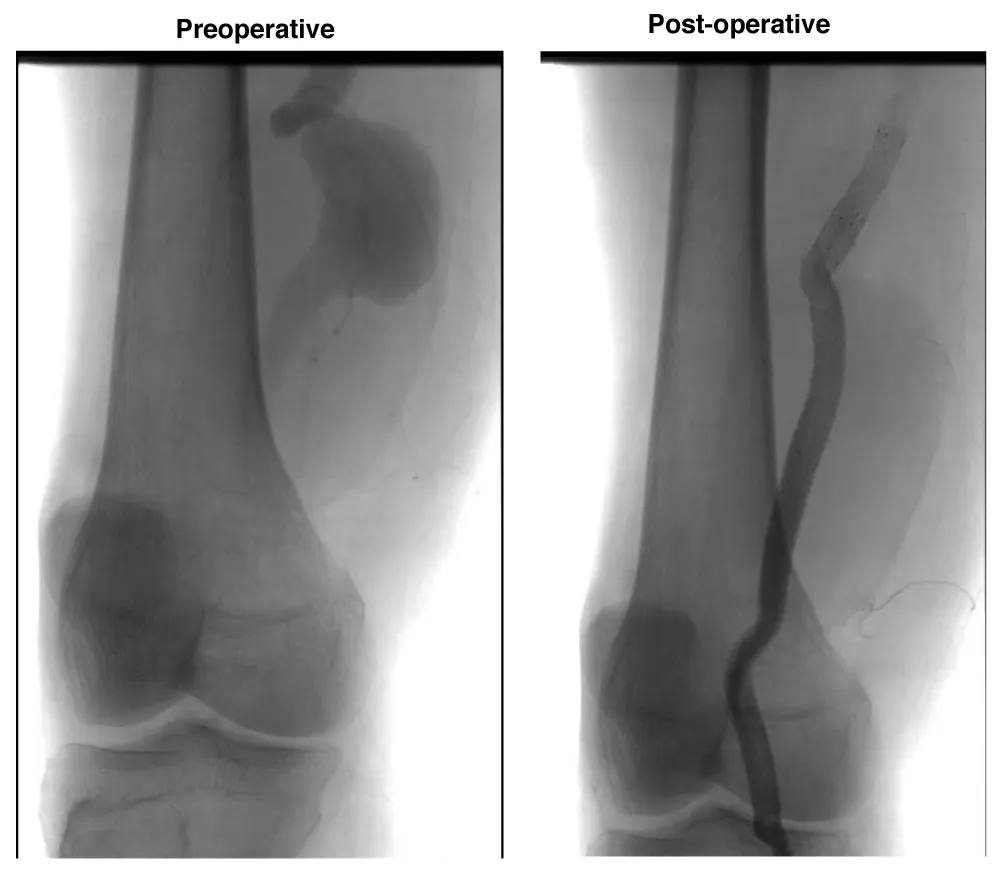

A male patient, 63 years, with arterial hypertension and dyslipidemia, was admitted with an asymptomatic popliteal artery aneurysm in the left Lower limb measuring 3,1 cm, discovered after an acute arterial occlusion at the right Lower limb due to popliteal artery aneurysm thrombosis. The following measures were observed: proximal neck diameter 10,21 mm, distal neck diameter 9,98 mm, with a diameter of 56 mm and 250 mm aneurysm length. The patient underwent endovascular treatment with the popliteal implant of endoprosthesis Wrapsody® 12x80 mm at the distal neck, followed by the implant of Wrapsody 12x125 mm and Wrapsody 12x80 mm at the proximal neck, followed by catheter balloon dilatation. The final image showed excellent results with no endoleaks (Figure 1). The patient was discharged from the hospital on the on the first postoperative day with Rivaroxaban 20 mg/day and a 6-month follow-up showed endoprosthesis patency with excellent flow and run-off.

Figure 1: Endovascular repair of a 63-year-old male with left popliteal artery aneurysm (56 mm): Preoperative imaging shows fusiform dilation of the popliteal artery. Postoperative image demonstrates successful deployment of three Wrapsody® endoprostheses (12×80 mm, 12×125 mm, and 12×80 mm) with complete exclusion of the aneurysm and no evidence of endoleak.